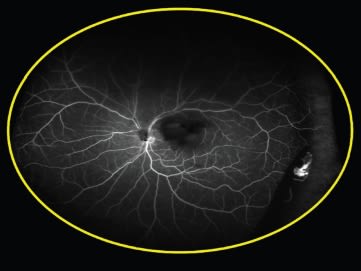

The second case Dr. Freund presented also used ultra widefield FA. This patient, a 55-year-old white woman, presented with what appeared to be posterior vitreous detachment–related symptoms, including the sudden onset of floaters related to a vitreous hemorrhage (Figure 1). The ultra widefield FA revealed instead that the problem arose from neovascularization related to peripheral nonperfusion; the fellow eye showed the same problem (Figures 2 and 3).

Figure 3. The fellow eye of the patient from Figures 1 and 2 also showed peripheral nonperfusion.